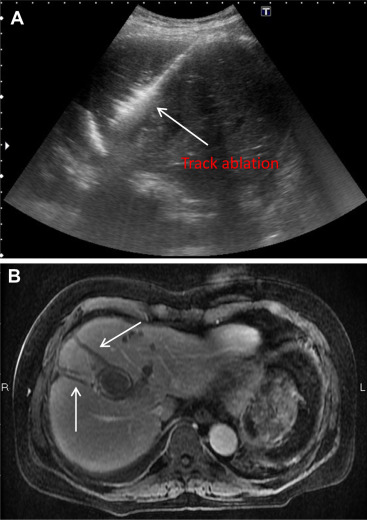

When all electrodes were withdrawn, track ablation was performed using a 40-W energy output to form a “comet-tail” appearance along the needle route on the ultrasound monitor.

Photographs of the non-touch technique and track ablation are presented in Figure 1 ; Figure 2 , respectively.

Figure 2. (A) Track ablation under 40 W energy output to form “Comet tail” appearance. (B) Evident track ablation shown in the following MRI. |

Track seeding is always a concern in percutaneous liver interventions such as liver biopsies or RFA. Tumor seeding after percutaneous RFA, with an occurrence rate as high as 12.5 % (4 of 32 cases), was reported by Llovet et al [16] in 2001. In another study from Taiwan, a 1.2 % track-seeding rate was reported [17] . These various seeding rates might be related to follow-up duration, the number of ablation sessions, whether tumor biopsies had been performed prior to RFA, and the completeness of the track ablation. In our study, no track seeding was observed during the follow-up period. Two reasons might account for this successful result. The most critical reason is the use of the non-touch approach: by avoiding contact with the tumor itself, the adherence of tumor cells to the electrodes was reduced, and track seeding during the advance and retraction of the electrodes was prevented. The second reason is that track ablation was strictly performed using a 40-W energy output. During each electrode retraction, we created a “comet-tail” image along the track on the ultrasound monitor. Hence, in the following spiral CT or MRI, the evident track ablation route can be clearly seen.